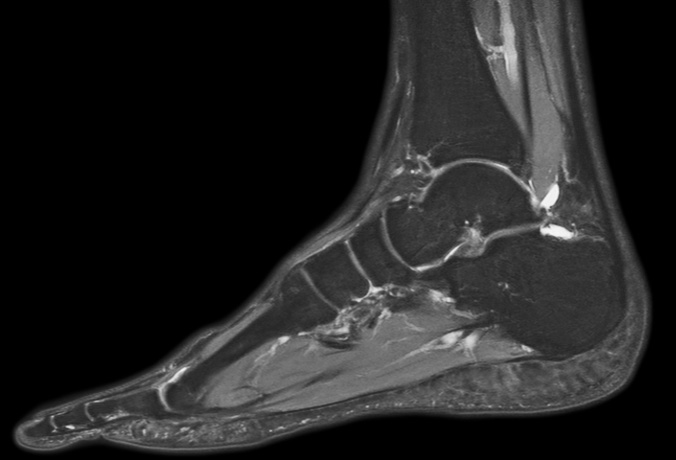

Sagittal PDw mDIXON TSE  (water only)